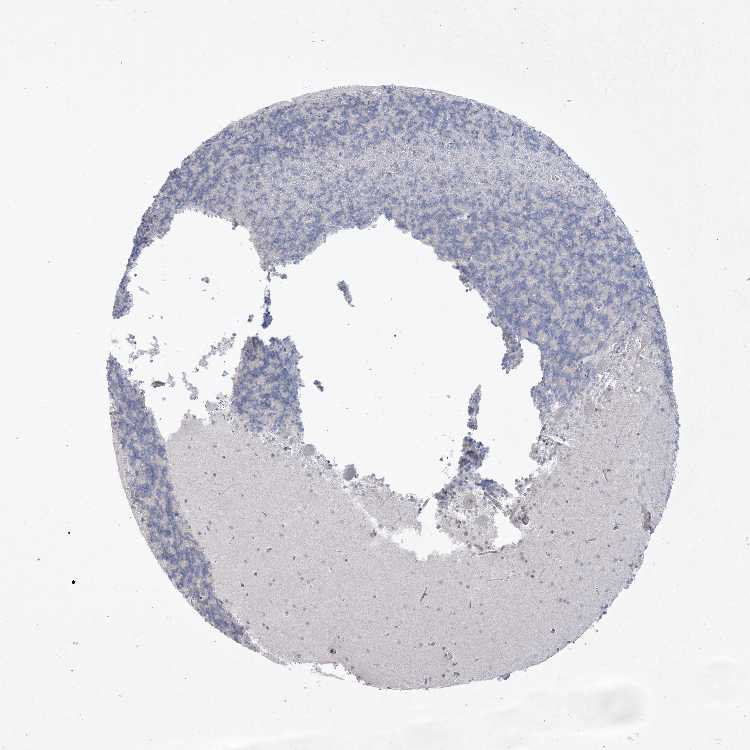

CEREBELLUM - Antibody stainingi

Antibody staining in the annotated cell types in the current human tissue is reported as not detected, low, medium, or high, based on conventional immunohistochemistry profiling in selected tissues. This score is based on the combination of the staining intensity and fraction of stained cells.

Each image is clickable and will lead to virtual microscopy that enables deeper exploration of all samples and also displays staining intensity scores, fraction scores and subcellular localization as well as patient and tissue information for each sample.

Antibody HPA036316Antibody HPA036317

Purkinje cells LowLow

Cells in granular layer Not detectedNot detected

Cells in molecular layer LowNot detected